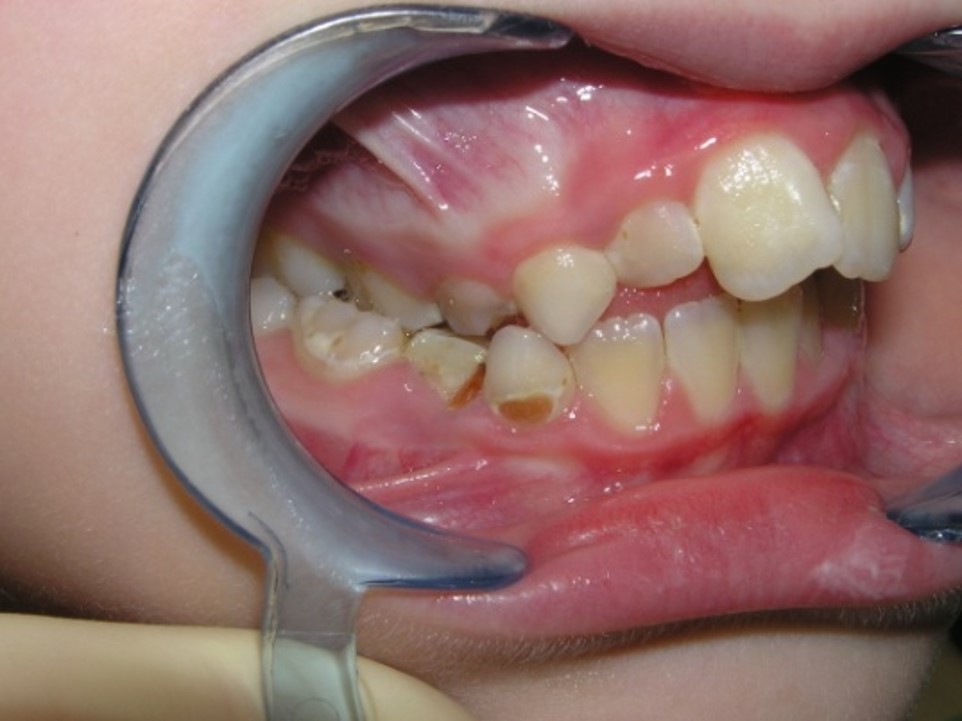

Tortoocclusion of teeth (rotation)

Tortoocclusion of teeth (syn. –

tortoanomaly, tooth rotation around the axis) is observed, more often in

permanent occlusion and less often in temporary occlusion. More often than other

teeth, the incisors of the upper and lower jaws rotate along the axis, less

often – canines, premolars and molars. The rotation of the tooth can be

insignificant (from 14ᵒ to 45ᵒ) and significant (from 90ᵒ to 180ᵒ).

Tortoocclusion of a tooth can be combined with other pathological occlusions of

the same tooth.

Pic.20. Tortoocclusion of teeth 11 and 21.